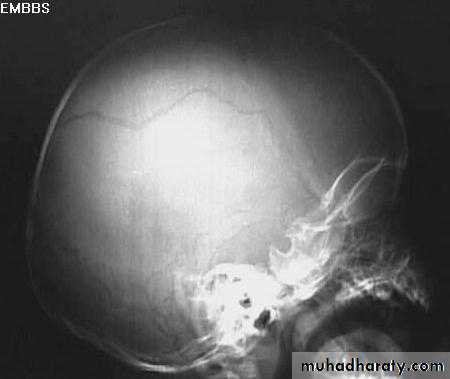

Skull Fracture

1. Can demonstrate the site and type of a skull fracture.2. A foreign body can also be seen.

Indications for skull x-ray in head injury

• Impaired consciousness or neurological signs.• History of loss of consciousness, amnesia, or fits.

• High speed injury or suspected penetrating injury.

• Scalp laceration to bone, large haematoma, or suspected fracture on palpation.

• Persisting vomiting or headache.

• Loss of cerebrospinal fluid or blood from ear or nose.

• Difficulty in assessing the patient (children, drug or alcohol intoxication).